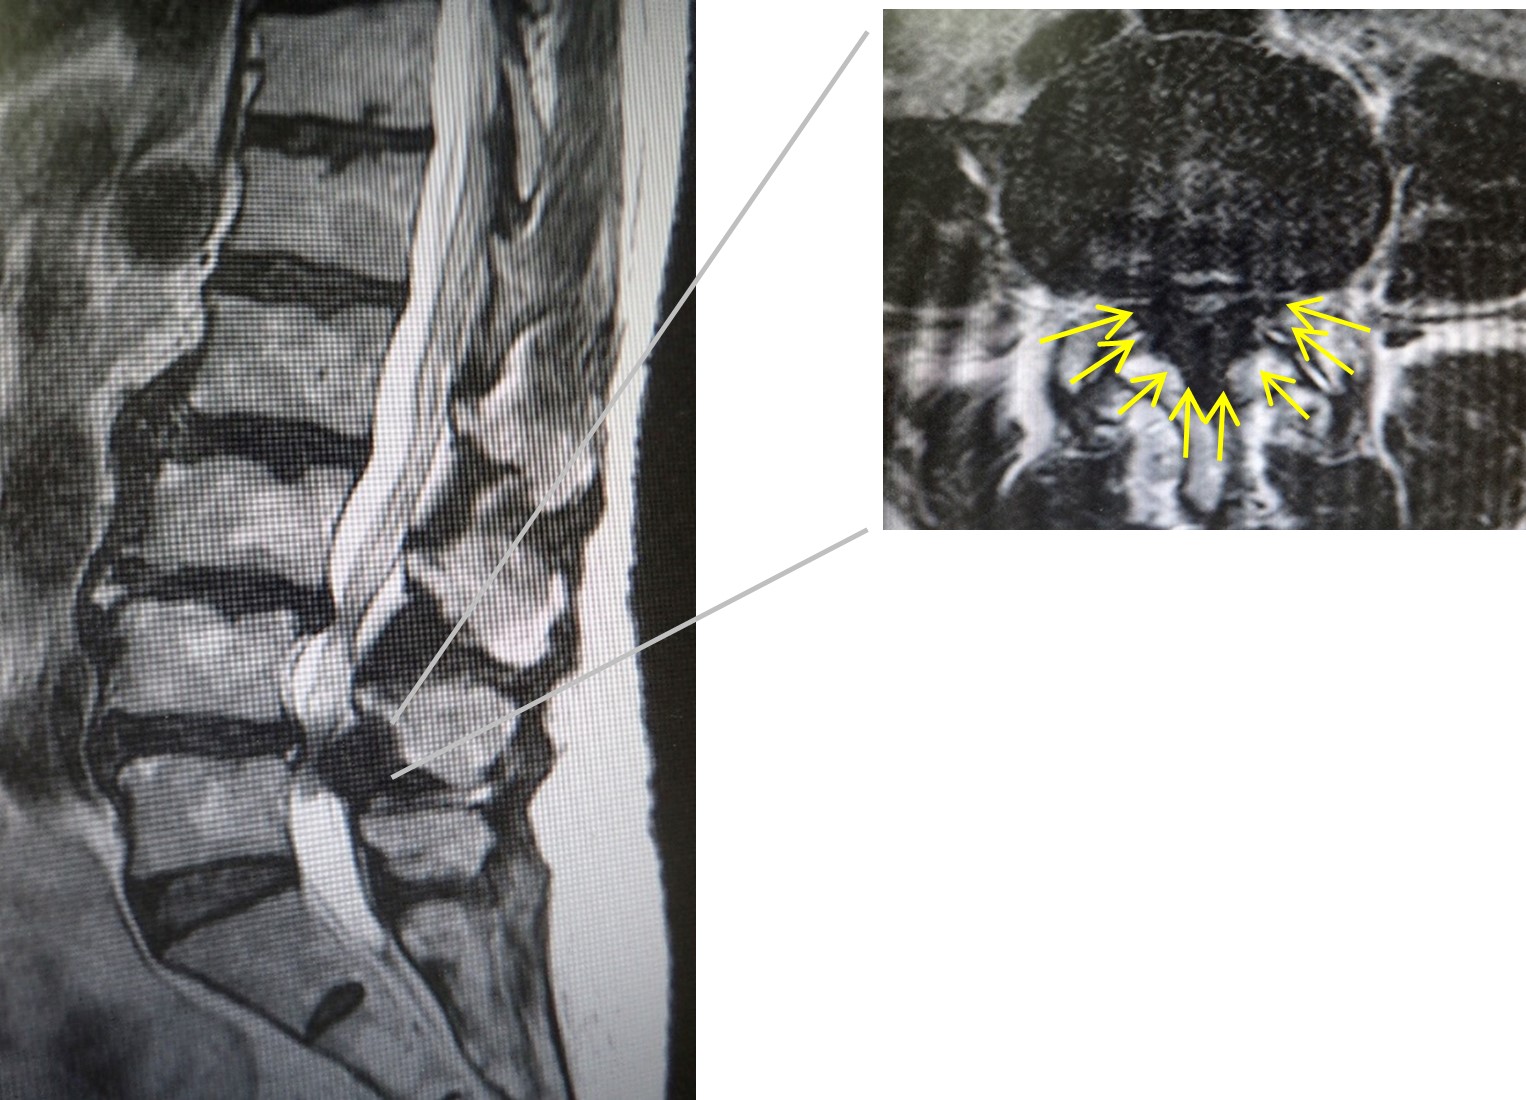

脊椎には、脊柱管と呼ばれる神経の通り道があります。加齢性変化などによって、腰部の脊柱管が狭くなると、下肢のしびれや痛み・脱力などを生じるようになり、この病態を腰部脊柱管狭窄症と呼んでいます。

治療は、まず薬物治療や神経ブロックなどの保存治療を行います。その他、コルセットなどの装具療法、あるいはリハビリテーションや減量指導なども行います。保存治療では改善が乏しく日常活動が制限されている場合、下肢の麻痺や膀胱直腸障害などの重篤な神経障害が認められる場合などには、手術治療を考慮します。腰部脊柱管狭窄症の手術は、腰部の骨や靭帯などを一部削り、狭くなった脊柱管を広げることで神経の圧迫を取り除きます。加えて、脊椎の不安定性がある場合は、金属製のスクリューなどで脊椎の固定や安定化を図ることもあります。石井医師は、十分に手術の適応を判断し、手術が必要な場合にはできるだけ最小侵襲(低侵襲)手術を取り入れ、術後早期にリハビリテーションを開始し、早期社会復帰を目指しています。

腰部脊柱管狭窄(症)の最小侵襲手術として、最小侵襲椎弓切除術、MIS-TLIF、LIF、CBTなどの手術方法があります。